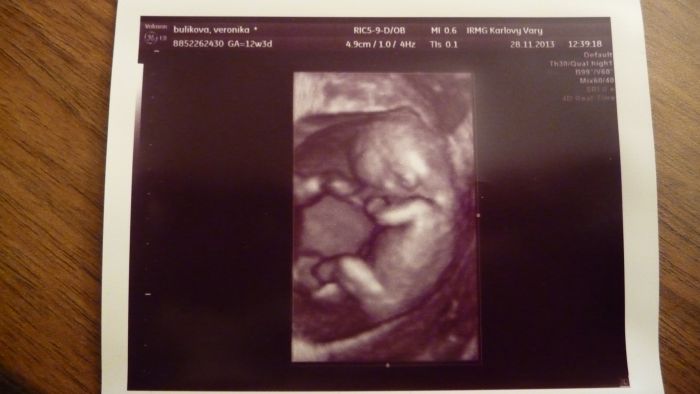

Ahojte těhulky, tak jsem dnes byla na screeningu, KONEČNĚ... ALE... čekám prý flegmatické spací mimčo

Doktor do mě bušil, musel mě vyšetřit vaginálně a mímo pořád spinkalo, vždy se jen zavrtělo, jako že nech mě a zase spinkalo. Vypadá prý vše ok, krev budou volat jen pokud něco objeví. Tak snad to bude také OK. Jinak máme 4,64 cm a Dr. mi řekl, že nejspíš nebudu v tom 12tt ale asi v 10tt. Tak nevím. Posune se mi TP, tak příští pondělí jdu na kontrolu k mé Dr. tak písnu. Srdíčko jsme s přítelem slyšeli a bylo to úžasné. Pohlaví nevíme, prý se nám správně nenatočila a je ještě brzy. Ale dva známí tatínkové na to koukali a bylo jim hned jasno. Viděli holčičku.

Tak snad se chlapáci taťáci nemýlili. Přítel byl na screen. celou dobu semnou a byl nadšený, nejvííc ze zvuku srdíčka. Mám 4 fotky a to jen proto, že to malé jen spalo, tak ho Dr. aspoň fotil. Bylo nádherné vidět toho tvorečka, jak si dává ručičky k obličeji a za hlavu. Jednu nožičku mělo nataženou a druhou pokrčenou. Jsem šťastná. Gratuluji maminám co ví už pohlaví.